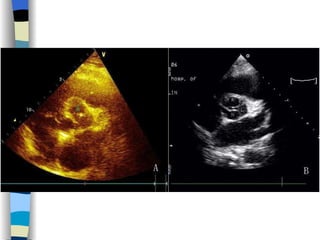

Echocardiography The most valuable technique for diagnosing MS, and determining its severity M-mode echo : Thickened, calcified leaflets open poorly, close slowly (EF slope ↓ ) The double peaks disappear Both leaflets move anteriorly during early diastole Two-dimensional echo: Fusion, thickening,  doming  of the valve leaflets, and poor leaflet separation in diastole;  mitral orifice area ↓

Echocardiography Establish a diagnosis, and determine the severity of AS M-mode and 2D echo  Observe aortic valve opening, thickening and calcification Helpful in determining the etiology of AS Also invaluable in detecting associated mitral valve disease and in assessing LV performance, hypertrophy, and dilatation

Echocardiography The mostvaluable technique for diagnosing MS, and determining its severity M-mode echo : Thickened, calcified leaflets open poorly, close slowly (EF slope ↓ ) The double peaks disappear Both leaflets move anteriorly during early diastole Two-dimensional echo: Fusion, thickening, doming of the valve leaflets, and poor leaflet separation in diastole; mitral orifice area ↓

Echocardiography Establish adiagnosis, and determine the severity of AS M-mode and 2D echo Observe aortic valve opening, thickening and calcification Helpful in determining the etiology of AS Also invaluable in detecting associated mitral valve disease and in assessing LV performance, hypertrophy, and dilatation